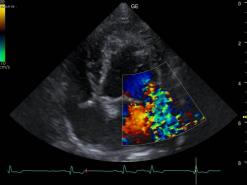

In der Ultraschalluntersuchung (Echokardiografie) werden die einzelnen Strukturen des Herzens und auch ihre Funktionen beurteilbar. Die Herzklappen, der Herzmuskel und der Blutfluss im Herzen wird dabei visualisiert.

Mit dem Ultraschall werden der Herzmuskel und seine Anhänge dargestellt. Die verdickten Klappenteile, das Ausmass des Pendelblutes, der vergrösserte Vorhof und Ventrikel sowie die Druckdifferenzen sind mess- und darstellbar. Nach dieser systematischen Erfassung und Beschreibung beurteilt die Tierärztin den Schweregrad der Erkrankung und definiert Therapie-Optionen.

Ausmass des Pendelblutes in den linken Vorhof in Farben.

Druckmessungen zwischen dem linken Vorhof und Ventrikel.

Farb-Doppler Darstellungen

dynamische subaorta- und midventrikuläre Obstruktionen führen zum links-Herzversagen

durch Rückfluss hochgradig vergrösserter Vorhof: Aorta/linkem Vorhof > 1.5

verdickte Ventrikelwand mit vergrössertem linkem Vorhof